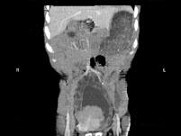

- 多项选择题男,33岁, 反复尿频,尿急, 尿痛3年余,排尿困难4月, 尿常规:蛋白(+), 红细胞0~1个/HP,白细胞(++), CT扫描如图所示,下列诊断哪项正确 ( )

A、膀胱结石

B、膀胱慢性炎性肉芽肿

C、膀胱癌

D、双侧肾积水,双侧输尿管扩张

E、膀胱多发性假性憩室